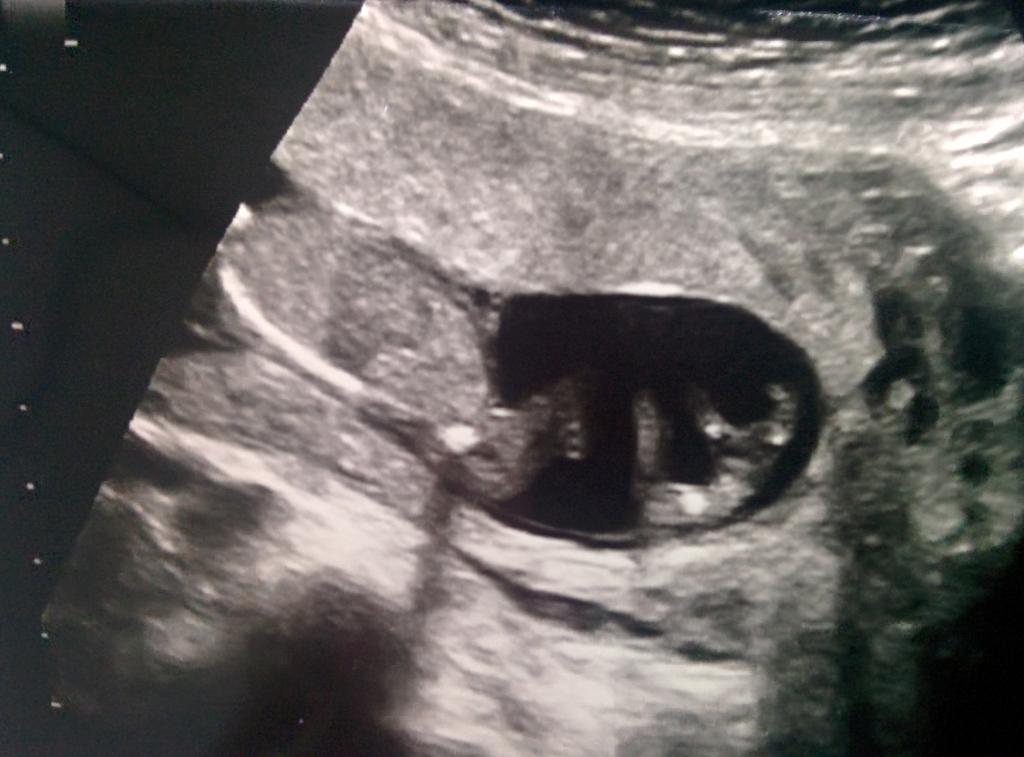

10 Week ultrasound - YouTube